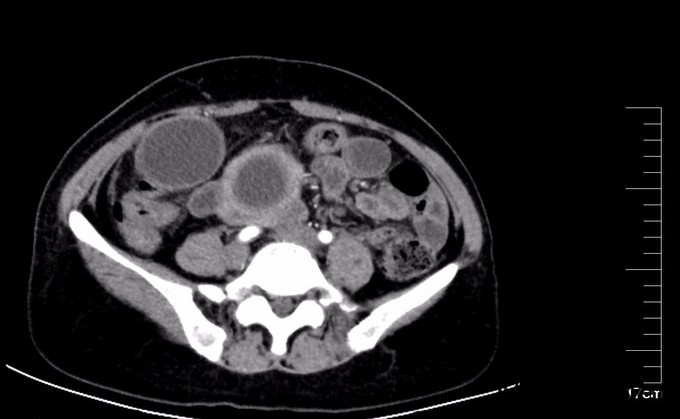

术后检测引流液淀粉酶,术后第一天引流液淀粉酶583U/L, 按照血淀粉酶正常值3倍定义胰瘘,存在胰瘘,术后第4日272 U/L,术后7日118 U/L,已经正常。复查腹部CT, 上腹壁见手术瘢痕影,腹壁下见少量渗出、积气;肝内胆管仍扩张、程度较前减轻,胆囊未见显示,胆囊窝留置导管、局部积气。胆总管囊肿病因不清,对此假说繁多,大多数病例被认为是先天性发育不良所致。胆管壁薄弱有认为管壁的支撑组织存在先天性缺损或存在异位胰腺组织使管壁处于低张状态;胆总管远端梗阻,致管内压力增加从而引起扩张。 分为三型:普通型,憩室型,十二指肠内胆总管膨出,本病例属于普通型。临床表现为间歇性上腹痛、右上腹肿块和黄疸,称为胆总管囊肿三联征,本病例无黄疸。一旦作出诊断,即应采取手术治疗,内引流为宜。胆总管囊肿不手术,会继发结石,并且恶变,本病例经过病理证实已经出现恶变倾向,早期尽快明确诊断,及时手术治疗是此病预防的关键。